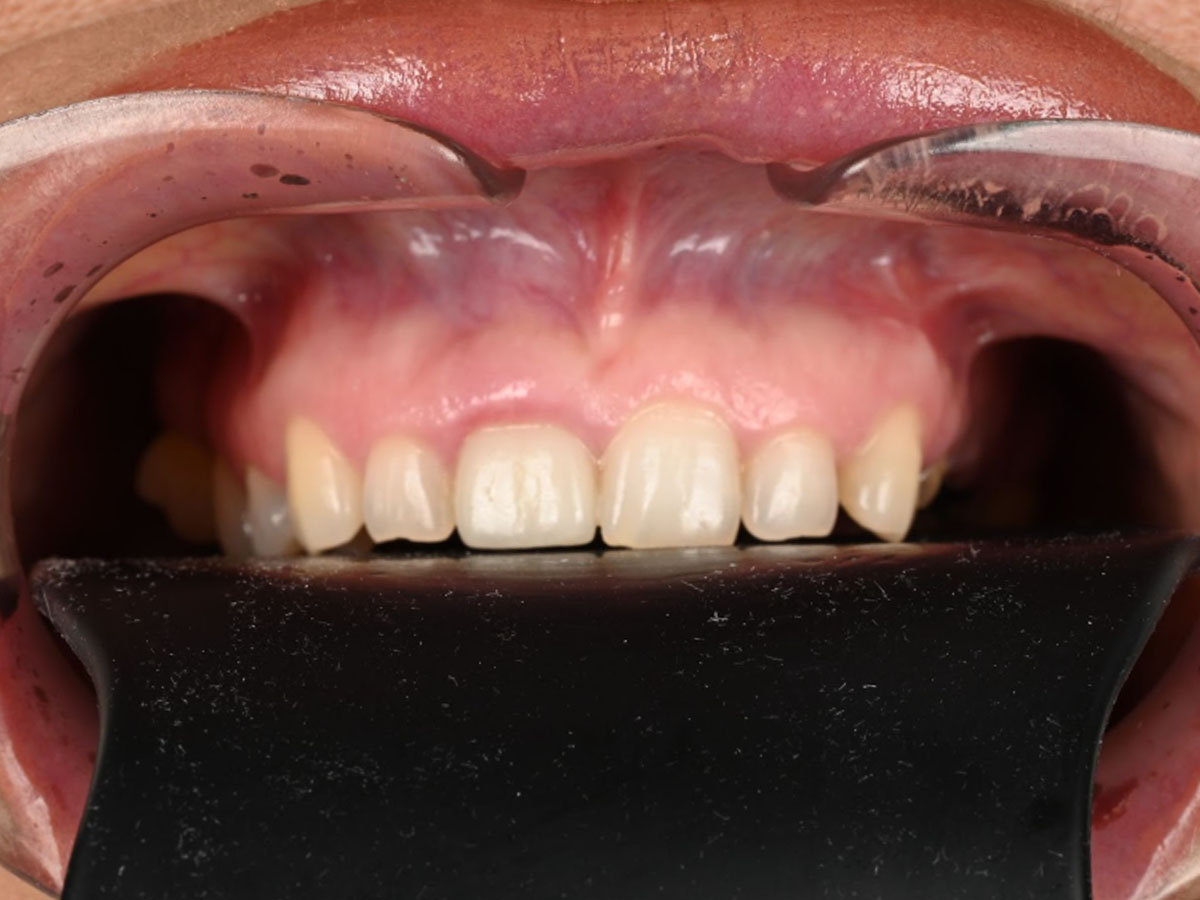

Un zâmbet complet reconstruit, printr-o abordare integrată și personalizată.

Pacienta a beneficiat de o reabilitare totală, atât la nivelul mandibulei, cât și al maxilarului, prin combinarea tratamentelor protetice pe implanturi și pe dinți naturali.

Această abordare complexă a oferit pacientei funcționalitate restaurată complet (masticație, vorbire), estetică echilibrată și naturală, confort și stabilitate pe termen lung.

Rezultatul este un zâmbet armonios, sănătos și complet funcțional, adaptat perfect trăsăturilor și nevoilor pacientei.